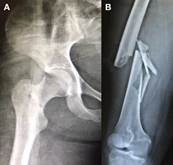

Las fracturas ipsilaterales proximales de fémur ocurren en el 1 al 9% de las fracturas diafisarias. La mayoría de las fracturas de cadera son del cuello, más que en la zona trocantérica, mientras que en la diáfisis ocurren más frecuentemente en tercio proximal y medio. Ocurren en pacientes jóvenes a causa de traumatismos de alta energía cinética como siniestros de tránsito o caídas desde grandes alturas, y obedecen a un mecanismo axial. En general, la mayoría de la energía se agota a nivel diafisario provocando fracturas conminutas (expuestas en ocasiones), mientras que la fuerza residual causa una fractura vertical sin desplazamiento a nivel basicervical (Figura 1). Dado esto último y que estas lesiones se dan en el contexto de un politraumatizado, desde un 20 hasta un 50% de las fracturas proximales pueden no ser diagnosticadas inicialmente.

Figura 1.  Patrón más característico en las fracturas ipsilaterales proximales y diafisarias de fémur. A: Fractura basicervical sin desplazamiento. B: Fractura conminuta del tercio medio de la diáfisis.